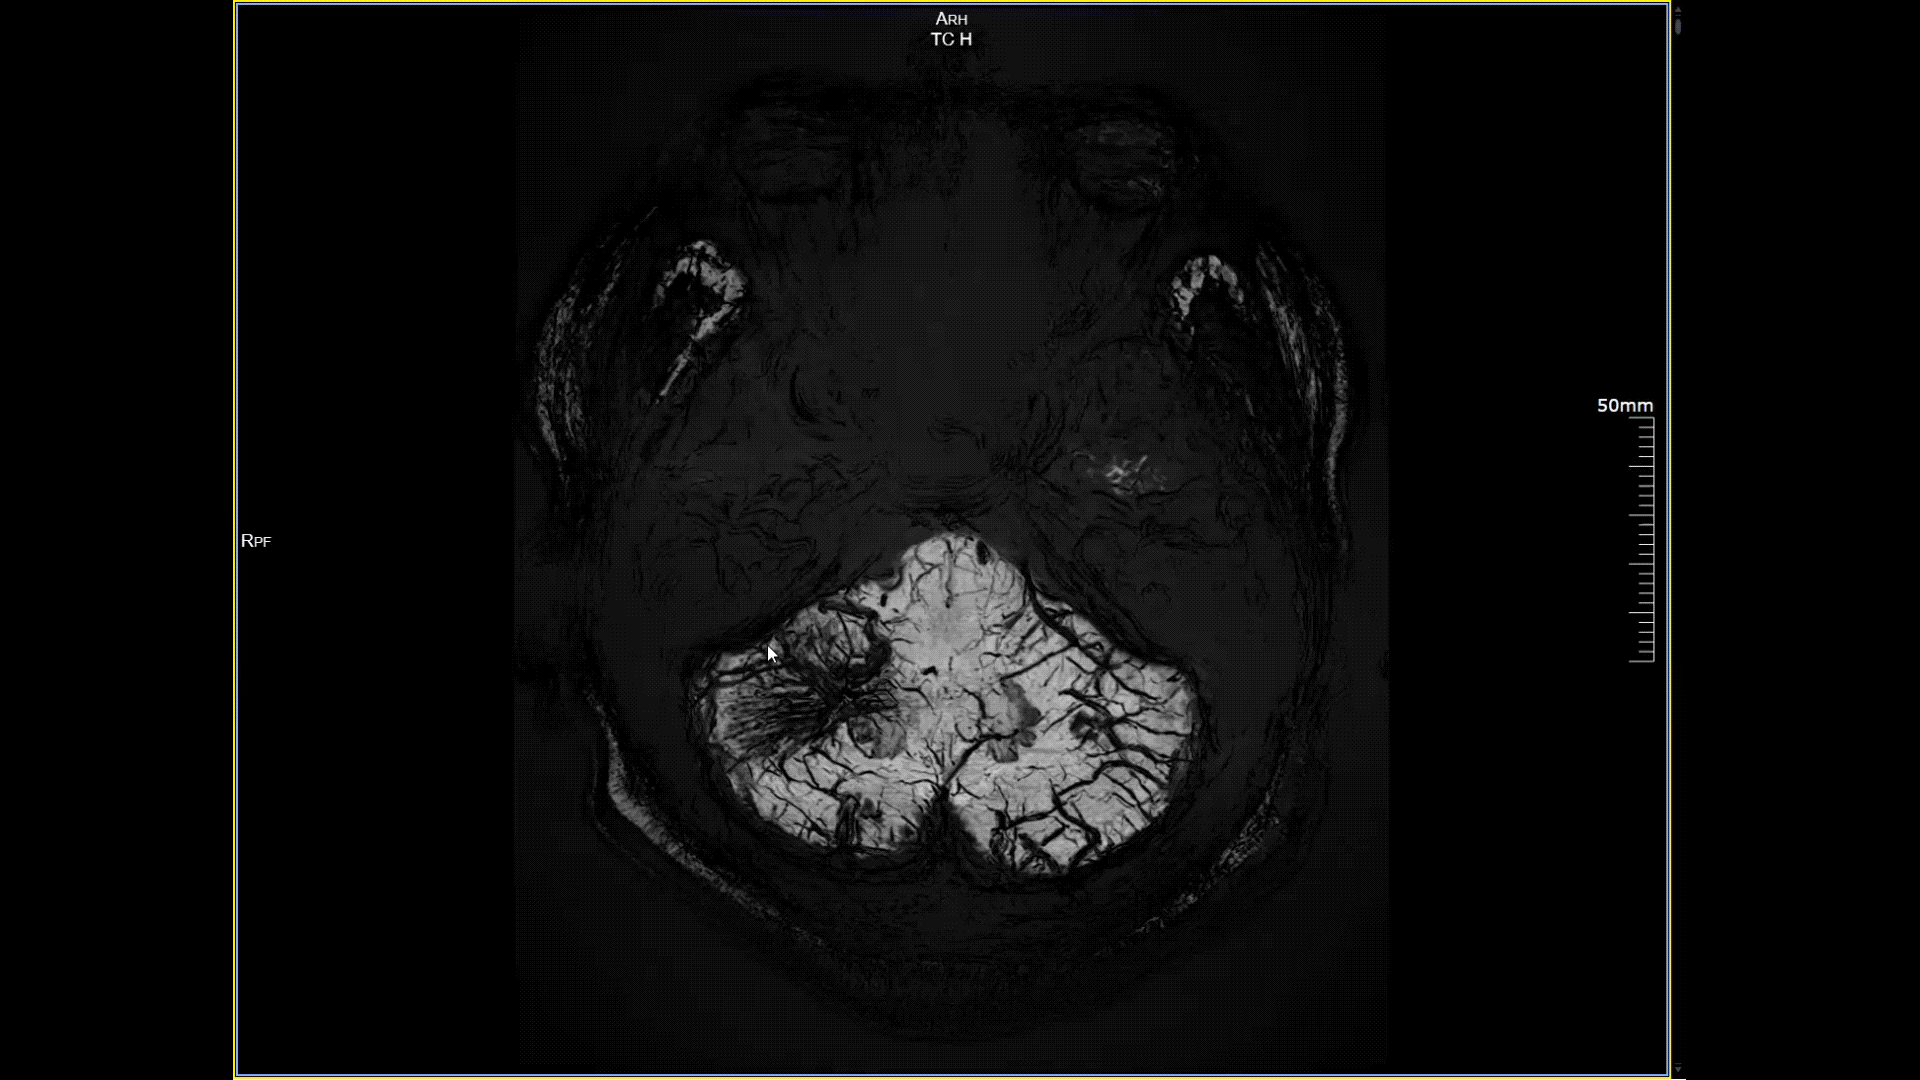

5.0T磁場強度遠高于其他設備,使得氫原子核在磁場中的響應信號極大地增強。這就像在安靜的房間里能聽清細微的聲音一樣,高信噪比能讓醫生看到更微小、更模糊的病變結構。例如上述患者的檢查,該設備可以呈現0.2x0.2毫米高分辨率的圖像以及動態顯示血管走行,使得病變血管的細微解剖結構、分布及其與周邊腦組織的關系得以直觀呈現,為臨床醫生進行精準診斷并制定后續治療方案提供了重要的影像學依據。

磁敏感成像SWI,分辨率0.2*0.2mm